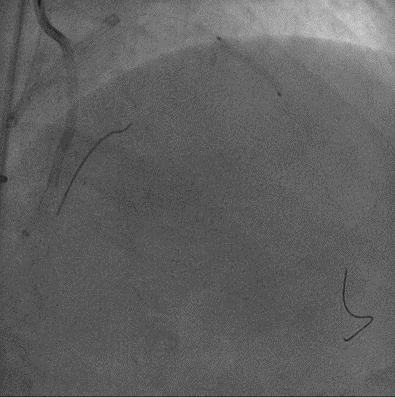

手术影像

左冠优势,LM、LCX未见狭窄,TIMI3级;LAD近段CTO,TIMI0级

RCA细小,近中段狭窄40%-50%,TIMI3级;远端可见LAD侧枝血流

策略讨论:近端纤维帽不清晰,LAD中段显影可见,闭塞段长度>20mm。间隔支逆供条件尚可。CTA提示LAD多发钙化。尝试正向开通,优选亲水性滑导丝,若失败,及时调整逆向策略。